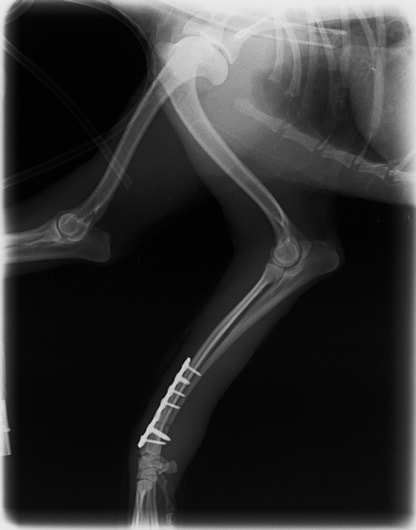

症例3:キルシュナーワイヤーのピンニングによる整復

ペルシャ猫 11ヶ月齢 雄

他院にて左大腿骨遠位の成長板骨折(salter-harrisⅠ型)が認められており、治療相談を目的として来院。当院にて、キルシュナーワイヤーを用いたピンニングにより骨折部位の整復を行いました。術後の経過は良好で、現在も経過観察中です。

術前レントゲン

術後レントゲン

機器

Arthrex社のターゲティングデバイスを用いてピンニングの位置を調整することで、確実な固定を行っています。当院ではこの手術器具以外にも、人の手術にも使用される様々な器具を導入し、手術精度を高め、また医療メーカーと新しい器具の開発、試作にも取り組んでおります。